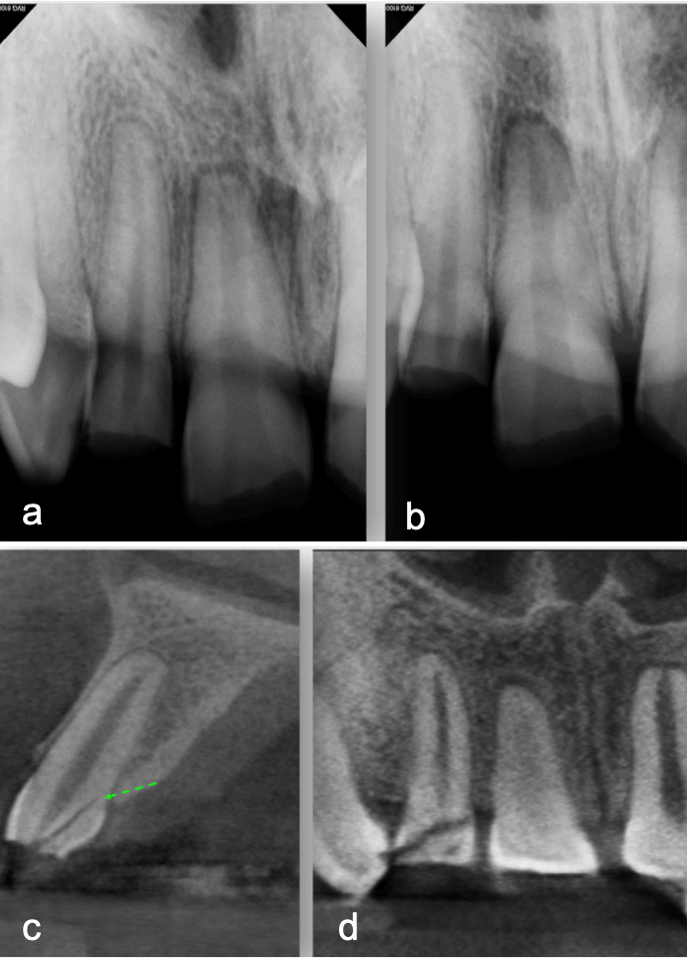

My first “wow” moment with CBCT was during the early years of the technology when scanning a patient after a traumatic dental injury that lead to lateral luxation of the maxillary left central incisor. The CBCT scan was able to produce images that previously had only ever been drawn or imagined. Those stunning 3D images have only gotten better over time. When indicated, 3D imaging provides critical information toward development of the best treatment plan. High-resolution images give endodontists the ability to change course and adapt quickly if needed to achieve better outcomes. Being able to diagnose a predictable failure also avoids unnecessary invasive procedures. For example, cases of root fractures or deep cracks (figure 1). For root canal retreatments understanding the etiology of the disease or failure is critical to obtain a positive outcome. CBCT also aids with enhanced visualization of traumatic injuries, particularly for crown, root fractures and luxation injuries (figure 2). Ultimately, the more accurate and realistic assessments of prognoses, the more predictable and positive outcome for my patients.

a-b. Periapical radiographs from different angles. Patient was referred for endodontic therapies on teeth 19 and 20 with apical lucencies consistent w